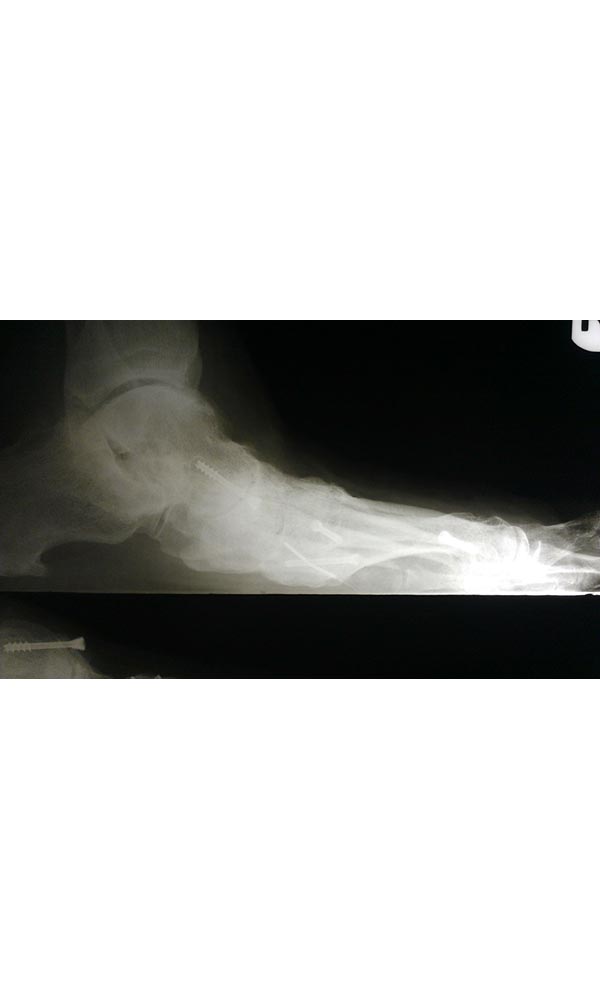

"Surgical misadventure" by another surgeon about 8 years ago. The wrong fixation was used for a flatfoot repair, & the deformity was not corrected. Patient came in with severe foot & ankle pain, with no arch at all. She was unable to play with her grandchild because the pain was so bad, & because she felt unsteady. The old hardware was removed, a lateral calcaneal lengthening osteotomy was performed along with a medial column/1st ray realignment. The ankle was painfully arthritic, & patient elected a total ankle replacement vs. an ankle fusion. She is now able to walk pain free & play with her grandchildren!